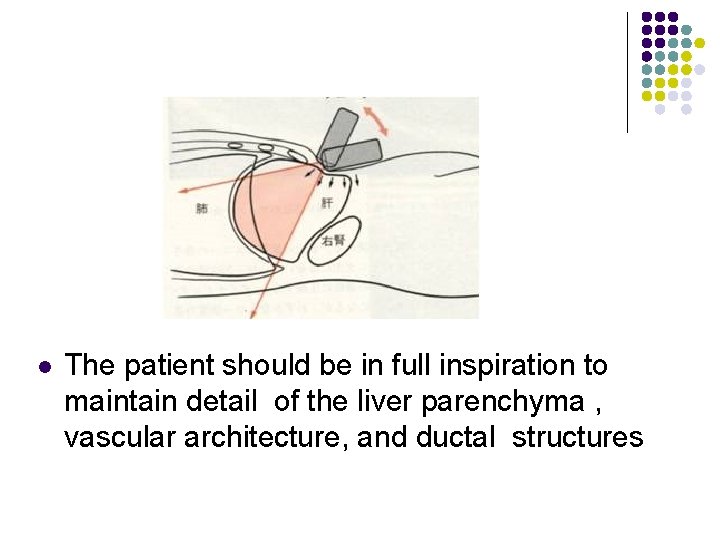

l The patient should be in full inspiration to maintain detail of the liver parenchyma , vascular architecture, and ductal structures